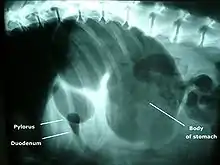

A diagnosis of GDV is made by several factors. The breed and history often gives a significant suspicion of the condition, and a physical examination often reveals the telltale sign of a distended abdomen with abdominal tympany. Shock is diagnosed by the presence of pale mucous membranes with poor capillary refill, increased heart rate, and poor pulse quality. Radiographs (X-rays), usually taken after decompression of the stomach if the dog is unstable, shows a stomach distended with gas. The pylorus, which normally is ventral and to the right of the body of the stomach, is cranial to the body of the stomach and left of the midline, often separated on the X-ray by soft tissue and giving the appearance of a separate gas-filled pocket (double-bubble sign).[4]